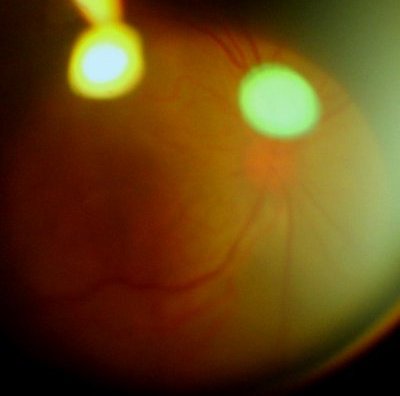

眼底像(前节照相机+90D,图像质量不高,见谅)

此主题相关图片如下:

右眼可见视网膜隆起,血管充血扩张,9点位视盘上线状出血